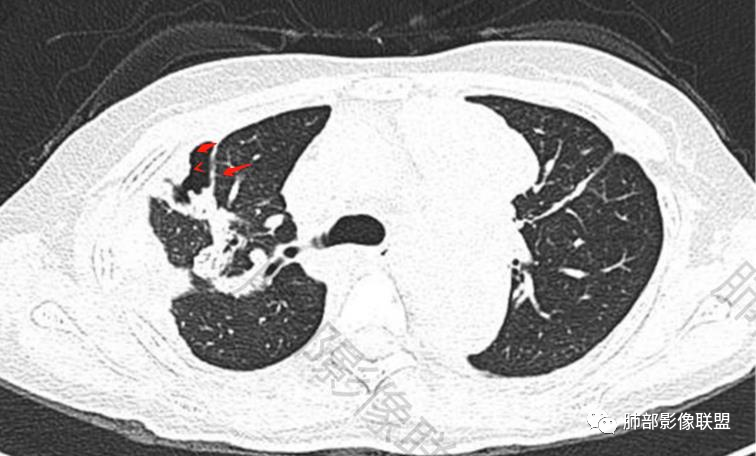

傅昌瑜:青年女性,咳嗽胸痛2月,偶有血痰。双肺上叶多发不规则肿块,密度不均匀,内部可见点状、条片状钙化影,右上肺病灶空洞,壁厚薄不均,见壁结节,与支气管关系不清,两侧胸膜增厚,见多发结节,部分结节边缘膨隆明显,结节内亦有多发钙化。上述改变常见于结核、尘肺、钙化性转移等疾病。有膨隆感的结节考虑转移可能性大。

尘缘:青年女性,痰中带血,胸痛2月,无发热盗汗,实验室检查,有贫血,总蛋白降低,血沉情况未知,肿标基本正常。影像表现:双上肺小叶间隔增厚,双侧胸膜广泛不规则增厚,胸膜下多发肿块伴不规则钙化,右侧肋骨破坏。纵隔淋巴结肿大不明显,双肺门淋巴结肿大,部分融合,分析思路:一、感染性病变,1、结核,青年女性,胸膜增厚,多发肿块伴钙化,有咳嗽胸痛,痰中带血,要考虑,但无结核中毒症状,病史仅两月却钙化太明显,肺内没有明显树芽征,存疑,2、其他感染,无炎性指标支持,白细胞不高,可能性小。二、非感染性病变,1、尘肺,胸膜增厚,钙化,胸膜下钙化性肿块,要考虑,但肺内无粉尘结节,无职业史,可能小。2、转移性钙化,无肾脏病史,无血清钙磷代谢异常指标支持,肺内间质无钙沉积改变,基本排除。三、肿瘤性病变,1、肺癌伴转移,双上肺有小叶间隔增厚,双肺门有淋巴结肿大,要考虑,但青年女性,病史两月,钙化太多太广泛,肿标基本正常,可能性小。2、骨肉瘤转移。15-30岁青年人,是骨肉瘤高发年龄,肺内多发成骨样钙化转移灶,双上肺小叶间隔增厚符合癌淋样表现,右侧肋骨破坏,要高度怀疑,需要详细询问病史及手术史。3、软骨来源肿瘤伴肺内转移,右侧肋骨虽有破坏,但无明显软骨样破坏及钙化。可能小。4、其他肿瘤伴转移,青年女性,其他恶性肿瘤能广泛发生钙化性转移的可能性小。综上所述:骨肉瘤伴右侧肋骨及胸膜转移,胸膜下转移,肺内癌淋可能最大,结核不完全除外,下一步需要,仔细询问病史,如果有骨肉瘤史,则基本确诊,如果没有,需要进一步问询呼吸系统症状,病程,以前的影像对照,了解肾脏情况,查血清钙磷指标。

右肺体积缩小,上叶见空洞影

上叶内多个结块,边缘有膨隆,内有钙化灶

钙化灶密度较高,环形/结节状

胸膜及附近肺内见多发结节/斑块

密度类似

边缘膨隆

部分区域有栽赃

空洞——恶性特点

胸膜结块,有侵袭性

但是都有多发钙化

结核?符合吗

不符合

空洞形成,一般伴随的很多都是气道的播散,树芽征

这个病例没有

空洞内壁算光滑,但是外侧的壁结节过于突兀

淀粉样变符合吗?也不符合。如果是淀粉样变,一般这么弥漫的钙化,肺门淋巴结都应该有钙化,而且侵袭性及肋骨表现都不支持淀粉样变性。